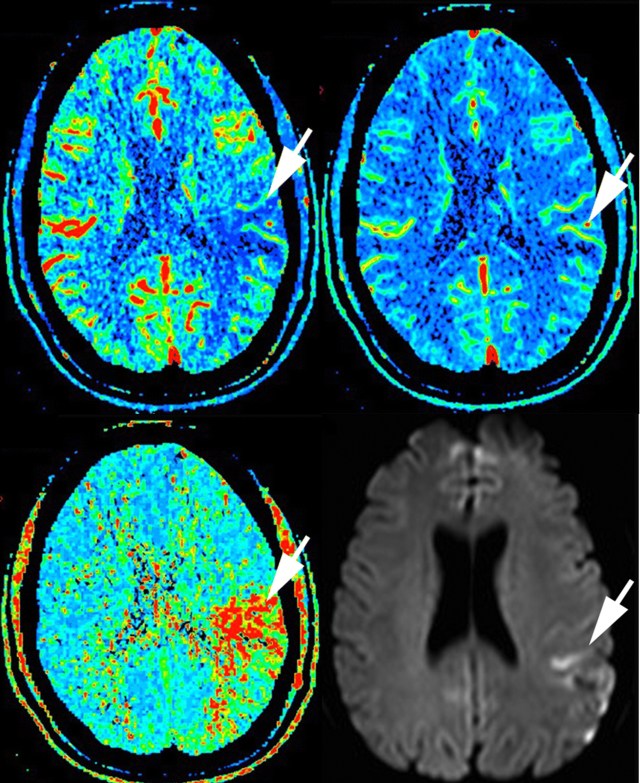

In a patient 70 minutes after stroke onset (NIHSS score 10), the unenhanced CT, not shown, is normal. The cerebral blood flow (top left) and cerebral blood volume (top right) show reductions in the arrowed area. There is a corresponding increase in mean transit time (bottom left) and a DWI weighted high signal area several days later on MRI (bottom right). (Figures taken from Hopyan et al., 2010.)

Cerebral blood flow is obviously reduced if there is a proximal thrombus, and in infarction there is reduction in cerebral blood volume. This could be because of tissue swelling raising local intracranial pressure and constricting capacitance vessels, because there is a certain elasticity in vessels so that constriction will follow from reduced flow, or because of reflex vasoconstriction of capacitance vessels in damaged brain. The reduced CBV is still less than the dramatically reduced flow, so that MTT is significantly prolonged. The infarcted area appears more blue on CBF and CBV and more red on MTT.

In ischaemic brain, the CBV is relatively preserved, perhaps because the affected brain area is not as swollen or perhaps because of preserved reflex capacitance vessel dilatation in an attempt to improve perfusion of these areas. Cerebral blood flow is reduced (blue), but there is now a mismatch between CBV (relatively normal) and MTT (clearly red).